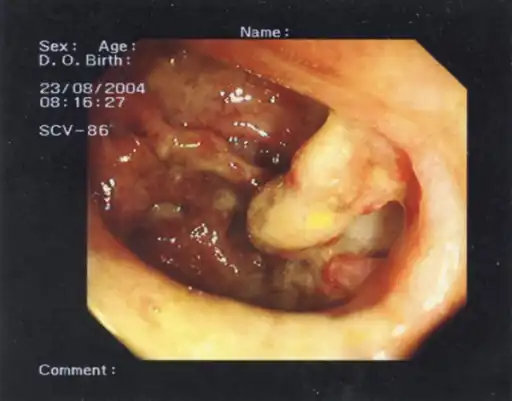

| Micrograph of pseudomembranous colitis, a cause of toxic megacolon. H&E stain. | |